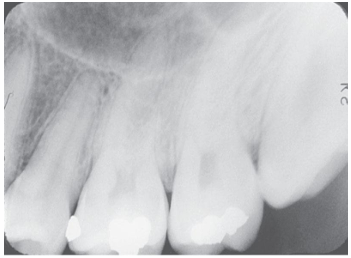

What is the problem with this Overlapped contacts X-ray?

Central ray not directed through the interproximal spaces

How would you resolve this Overlapped contacts X-ray?

Direct the x-ray beam through the contacts